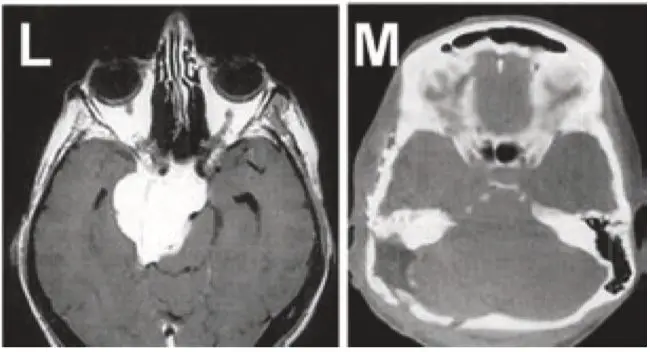

图L+M:展示岩斜区脑膜瘤患者术前术后影像对比结果。